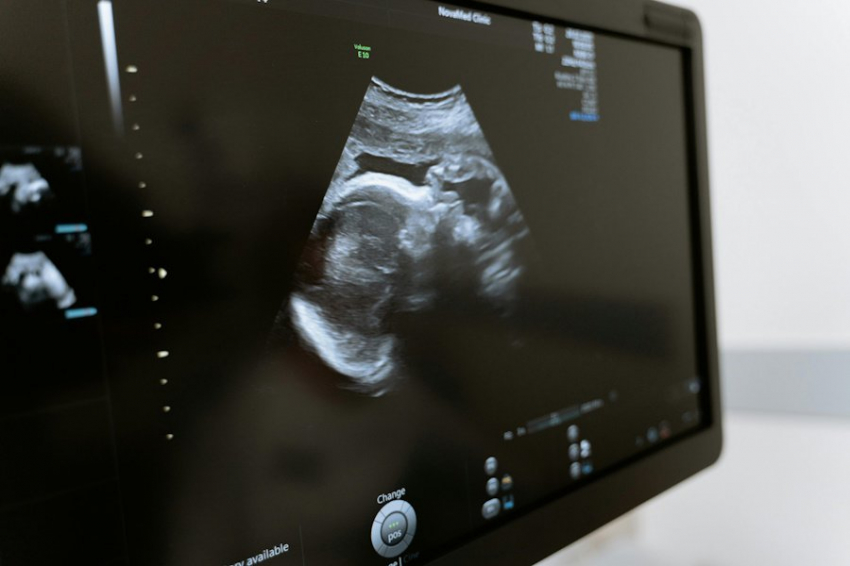

В США роженица родила тройню, а затем впала в состояние клинической смерти. В нем она провела 45 минут. Врачам удалось вернуть американку к жизни. Однако после того, как женщина пришла в себя, у нее временно пропала память - она напрочь забыла о родах. Удивительную историю 30-летней Марисы Кристи рассказало издание TODAY.com.

Американка была на последнем месяце беременности и обратилась в клинику для проведения планового кесарево сечения

Во время операции все было нормально. Медикам удалось извлечь девочек из живота матери. Они готовились обрезать младенцам пуповину, когда Кристи внезапно забилась в конвульсиях, а сердце ее остановилось.

У роженицы, как выяснилось, случилась эмболия амниотической жидкости (ЭАЖ), при которой окружающая ребенка жидкость в утробе после родов попадает в кровь женщины и провоцирует аллергическую реакцию. Это крайне редкое осложнение для 80-85 процентов пациенток, с ним столкнувшихся, оказывается смертельным.

Кристи повезло. Ее вовремя начали реанимировать, а затем, чтобы не допустить повреждений мозга, подключили к ЭКМО. Клиническая смерть американки длилась 45 минут.

Чтобы вывести аллерген из крови, врачам пришлось перелить пациентке много крови.

В себя Мариса пришла только спустя неделю. При этом выяснилось, что роды совершенно стерлись у нее из памяти. Она не признавала факта рождения троих дочерей. Врачам пришлось прилагать усилия, чтобы восстановить связь между матерью и детьми.